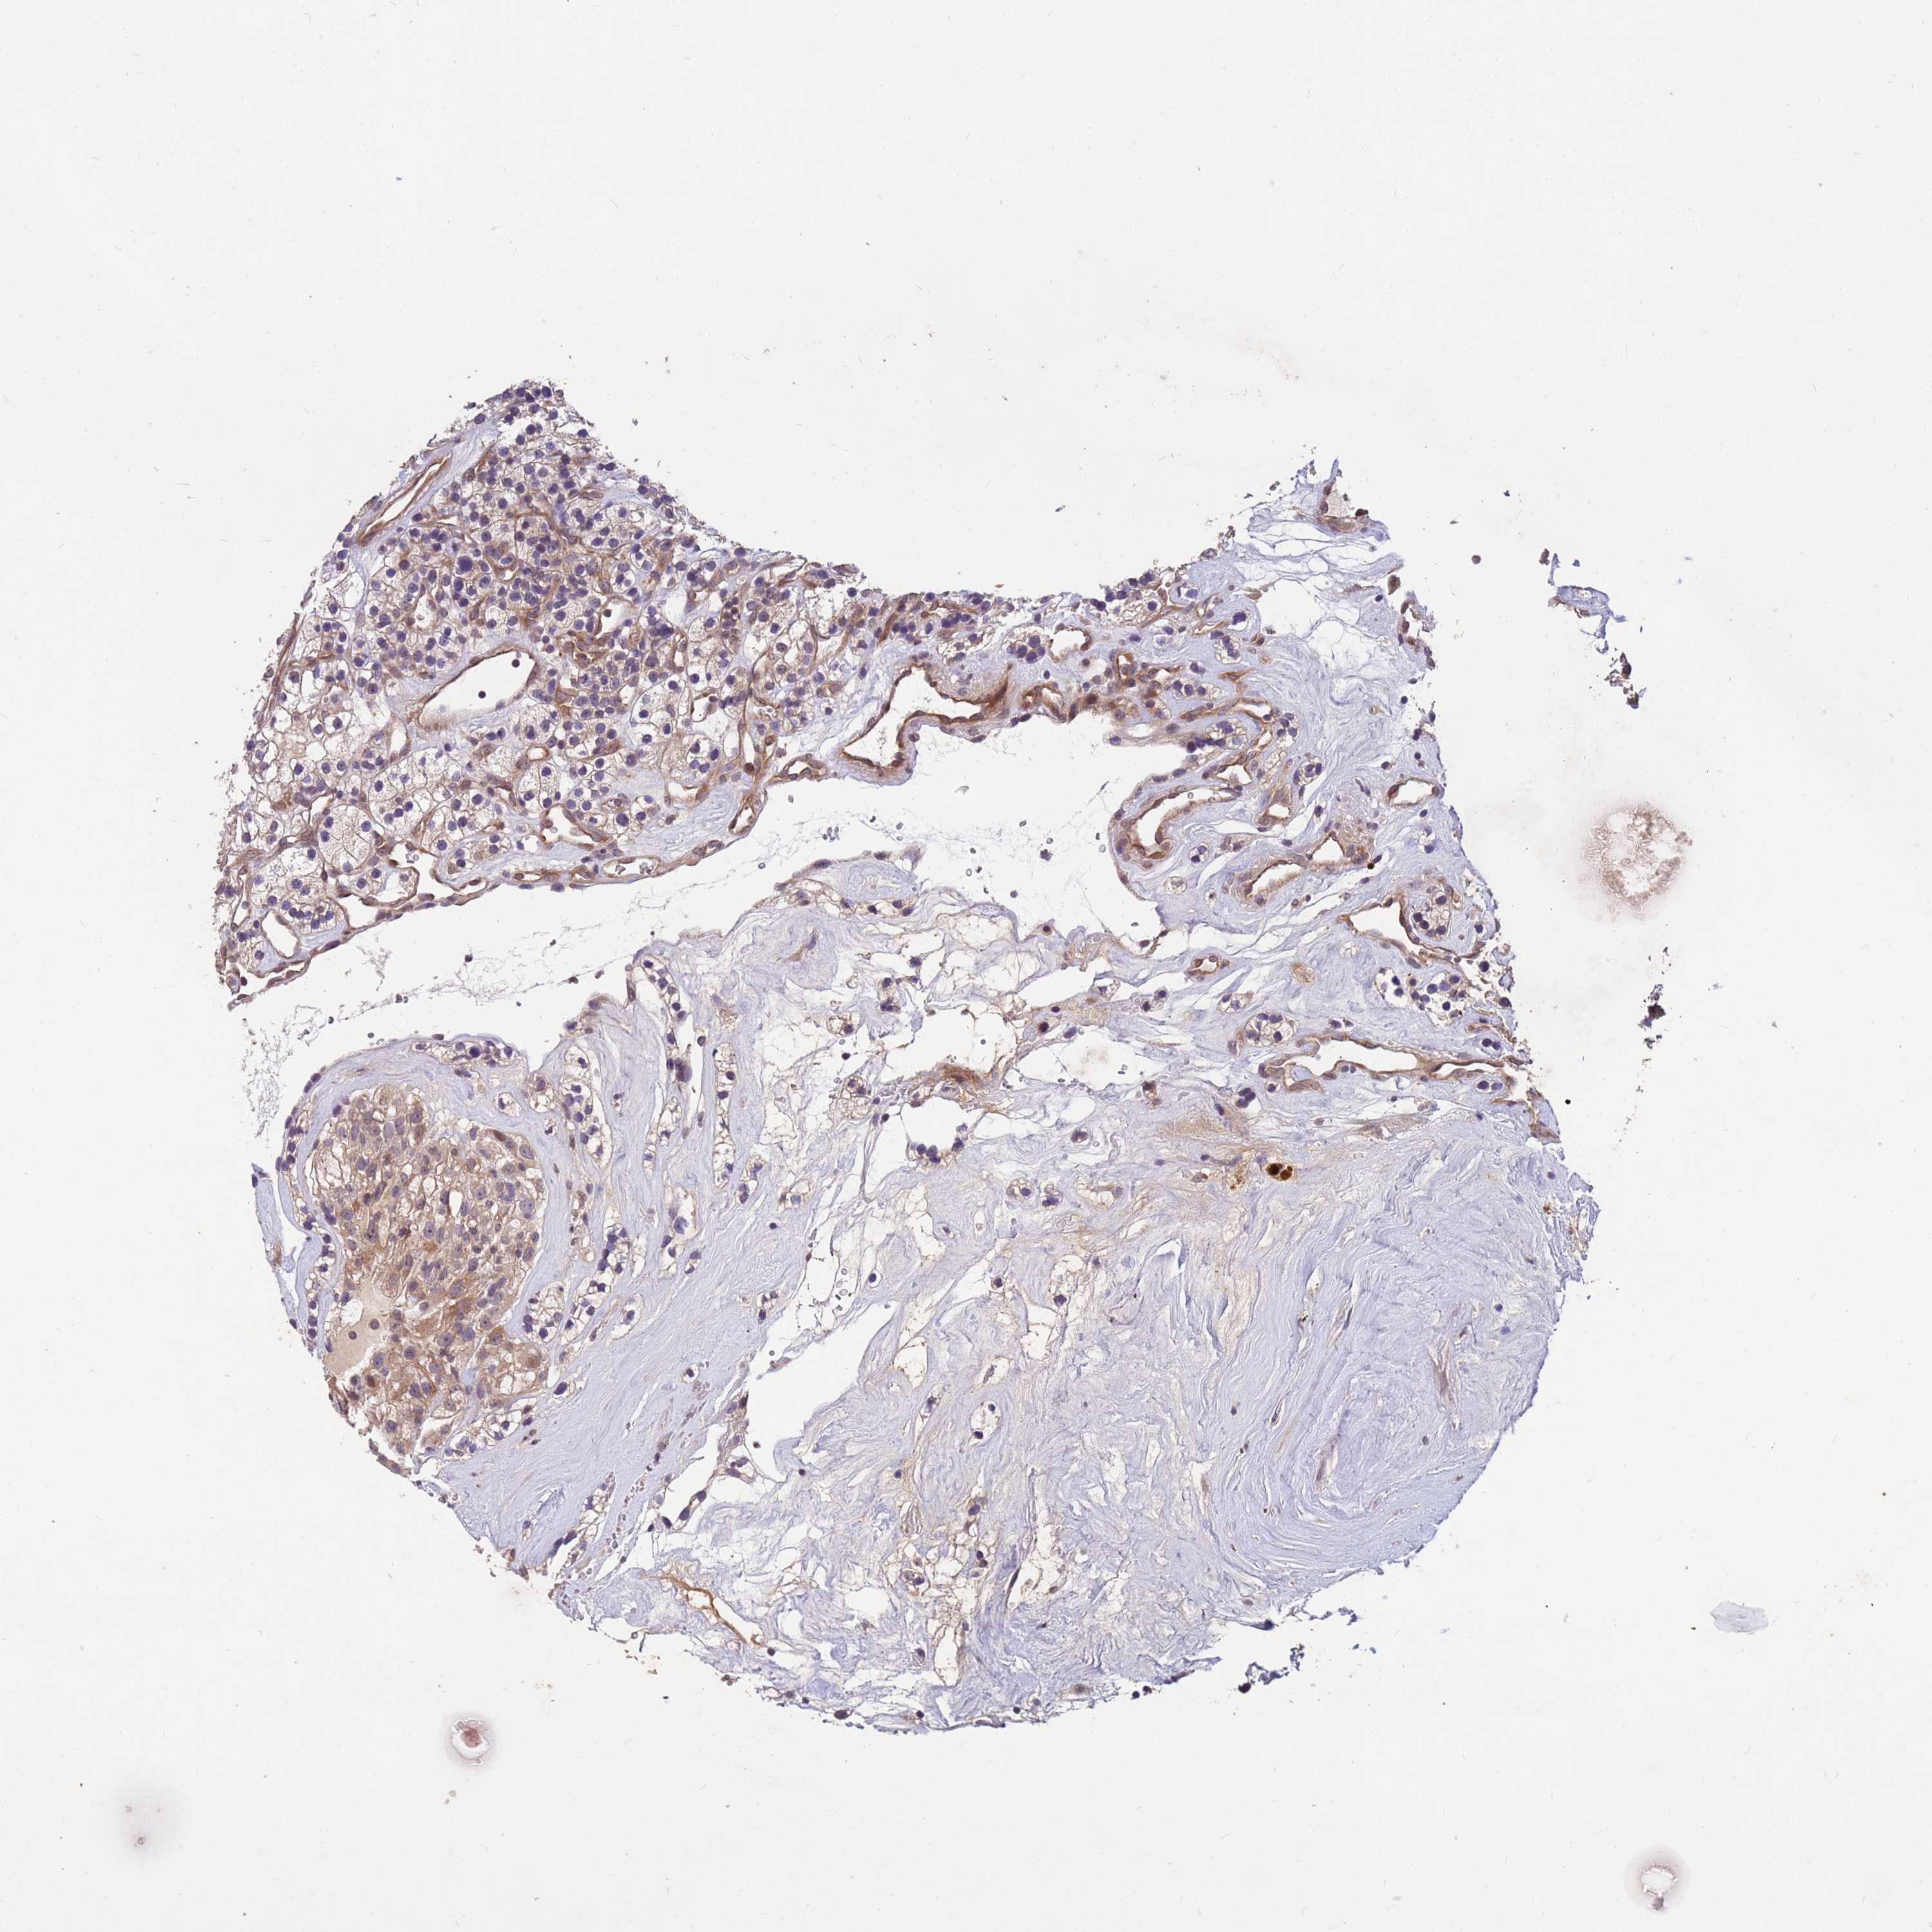

KIDNEY RENAL CLEAR CELL CARCINOMA (VALIDATION) - Interactive survival scatter ploti

The Survival Scatter plot shows the clinical status (i.e. dead or alive) for all individuals in the patient cohort, based on the same data that underlies the corresponding Kaplan-Meier plots. Patients that are alive at last time for follow-up are shown in blue and patients who have died during the study are shown in red.

The x-axis shows the expression levels (FPKM) of the investigated gene in the tumor tissue at the time of diagnosis. The y-axis shows the follow-up time after diagnosis (years). Both axes are complimented with kernel density curves demonstrating the data density over the axes. The top density plot shows the expression levels (FPKM) distribution among dead (red) and alive patients (blue). The right density plot shows the data density of the survived years of dead patients with high and low expression levels respectively, stratified using the cutoff indicated by the vertical dashed line through the Survival Scatter plot. This cutoff is automatically defined based on the FPKM cutoff that minimizes the p-score. The cutoff can be changed by dragging the vertical line or by entering a cutoff value in the square labeled "Current cut-off".

Under the Survival Scatter plot the p-score landscape (black curve; left axis) is shown together with dead median separation (red curve; right axis). Dead median separation is the difference in median mRNA expression between patients who have died with high and low expression, respectively. It is calculated as follows: median FPKM expression of dead patients with high expression - median FPKM expression of dead patients with low expression. This is intended to aid the user in visually exploring custom cutoffs and the associated p-scores and dead median separation.

Individual patient data is displayed and can be filtered by clicking on one or more of the category buttons on the top of the page. Categories describing expression level and patient information include: high, low, alive, dead, female, male and tumor stages. The scale of the x-axis can be toggled between linear and log-scale by clicking on the "x log" button. Mouse-over function shows TCGA ID, patient information and mRNA expression (FPKM) for each patient.

& Survival analysisi

Kaplan-Meier plots summarize results from analysis of correlation between mRNA expression level and patient survival. Patients were divided based on level of expression into one of the two groups "low" (under cut off) or "high" (over cut off). X-axis shows time for survival (years) and y-axis shows the probability of survival, where 1.0 corresponds to 100 percent.

PPP2CB is not prognostic in Kidney Renal Clear Cell Carcinoma (validation)

Best expression cut offi

Based on the FPKM value of each gene, patients were classified into two groups and association between prognosis (survival) and gene expression (FPKM) was examined. The best expression cut-off refers the FPKM value that yields maximal difference with regard to survival between the two groups at the lowest log-rank P-value. Best expression cut-off was selected based on survival analysis .

When clicking on this number, the vertical dashed line indicating cut-off, the interactive survival plot, and the Kaplan-Meier curve will be adjusted to show results based on the best expression cut-off.

: 71.82

Median expressioni

Median expression refers to the median FPKM value calculated based on the gene expression (FPKM) data from all patients in this dataset. When clicking on this number, the vertical dashed line indicating cut-off, the interactive survival plot, and the Kaplan-Meier curve will be adjusted to show results based on the median expression.

: N/A

Median follow up timei

Median follow up time refers to the median time (years) after diagnosis with this type of cancer, based on clinical data from all patients in this dataset.

P scorei

Log-rank P value for Kaplan-Meier plot showing results from analysis of correlation between mRNA expression level and patient survival.

N/A

5-year survival highi

5-year survival for patients with higher expression than the expression cutoff.

For melanoma and glioma, 3-year survival is shown.

5-year survival lowi

5-year survival for patients with lower expression than the expression cutoff.

TCGA RNA samplesi

RNA-seq data is reported as average FPKM (number Fragments Per Kilobase of exon per Million reads), generated by the The Cancer Genome Atlas (TCGA) .

Normal distribution across the dataset is visualized with box plots, shown as median and 25th and 75th percentiles. Points are displayed as outliers if they are above or below 1.5 times the interquartile range. FPKM values of the individual samples are presented next to the box plot.

Average pTPM 110.0

Number of samples 100